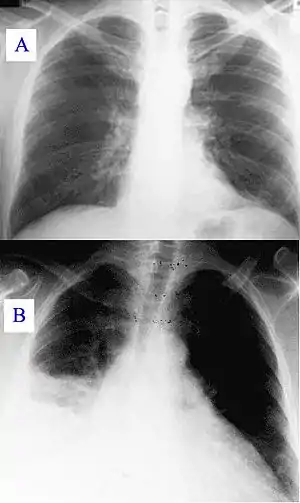

During its course, the disease can progress to an atypical pneumonia, which can result in a life-threatening acute respiratory distress syndrome, whereby such symptoms usually occur during the first four to five days of infection.[7]